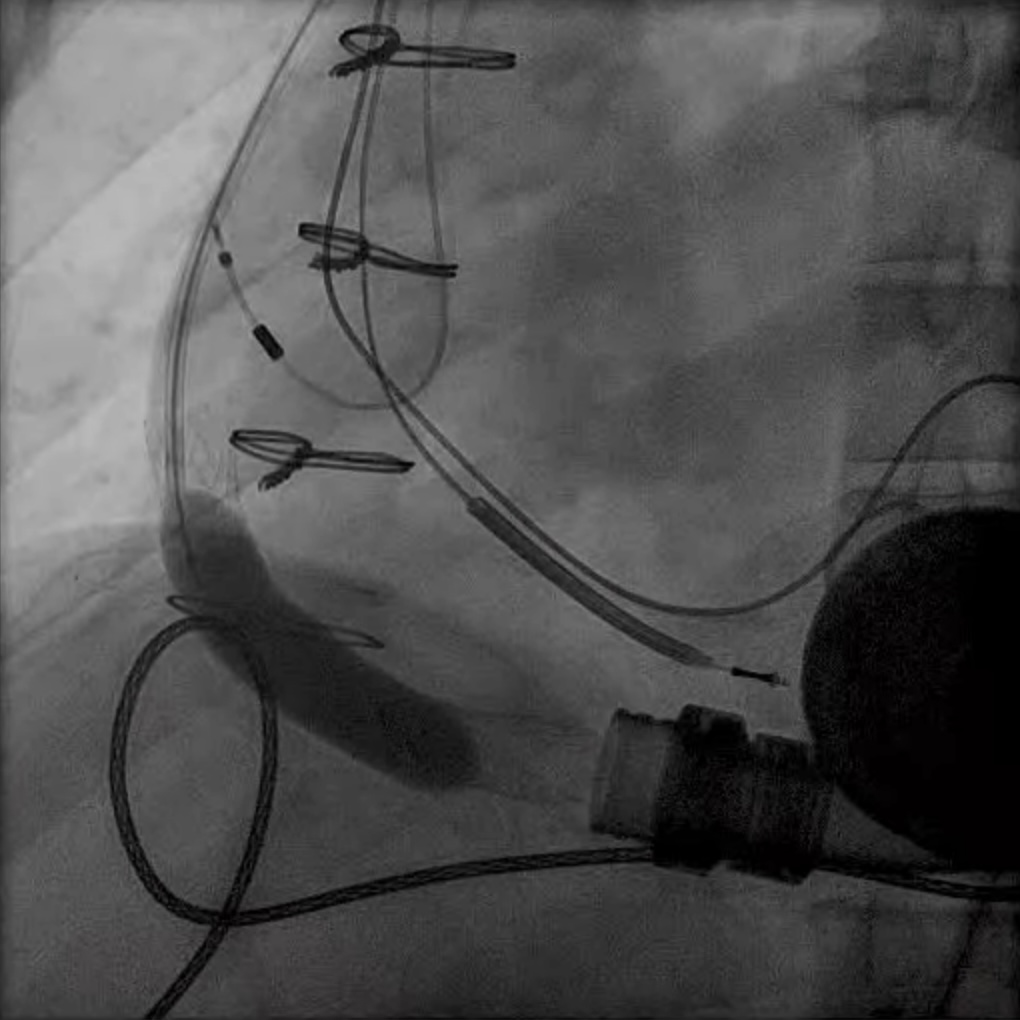

In LVAD patients that have had prior ring annuloplasty repairs and severe tricuspid regurgitation, transcatheter TV replacement is an option utilizing commercially available TAVR valves in a surgical ring approach. Our group successfully performed valve-in-ring TTVR in an LVAD patient with severe TR refractory to medical treatment (Fig. 8a). T-TEER in an LVAD patient (Fig. 8b) has been performed by our group and others [29]. As discussed above CIED leads are present in a large portion of LVAD patients and this approach may not be as successful given the anatomical challenges including large coaptation gaps (

Fig. 8. Tricuspid valve valve-in-ring TTVR in LVAD patient. (a) Sapien 3 valve being deployed in a TV annuloplasty band for treatment of severe TR via trans jugular approach. (b) T-TEER with Triclip. Torrential to mild TR after three Triclips. (Two previously placed Mitraclips are also visible on the fluoroscopy image). T-TEER, tricuspid transcatheter edge to edge repair; TV, tricuspid valve; TR, tricuspid regurgitation.